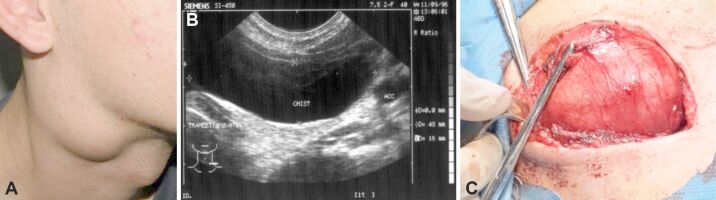

The discovery of a cervical mass in children is a situation quite frequently encountered and often represents a diagnostic or therapeutic challenge for the practicing physician. Although approximately 12% to 15% of all neck masses (NMs) in children may be malignant, most commonly these masses are benign. This study included 137 patients aged between 14 months and 18 years old, with the majority (54.01%) of patients being less than five years old. A total of 83 (60.58%) patients were presented with a single NM, with 64 (59.12%) patients having mass located on the midline of the neck. Preoperatively, in addition to laboratory tests, imaging examinations played an important role in diagnostic orientation and determining the therapeutic plan. Among the imaging examinations, ultrasound was the most commonly used, performed in 87 (63.5%) of the patients. The definitive diagnosis was established based on the histopathological examination of the excised specimens. Midline NMs were most frequently thyroglossal duct cysts or dermoid cysts, while lateral NMs were often lymphadenitis or branchial cysts. The aim of this study was to present the experience of 10 years in evaluating cervical masses in the neck area that appeared in children, their possible causes, the methods of investigation (considering the contribution and limitations of each diagnostic method), and the therapeutic approach (since there is no clear standardization of treatment in the literature).